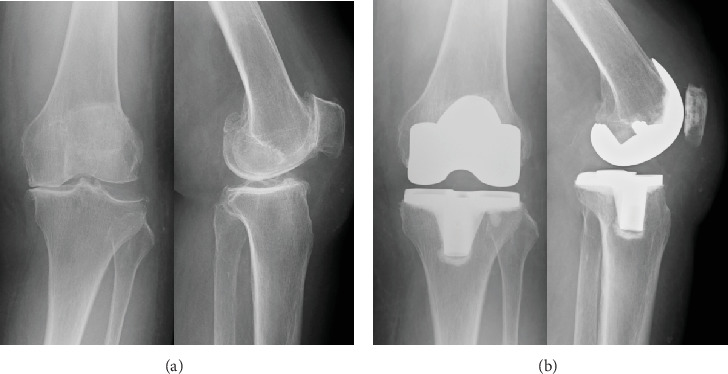

Herein, we present a rare case of periprosthetic joint infection (PJI) which was triggered by an infection with a latent subcutaneous cyst on the thigh and occurred in a strange course following total knee arthroplasty (TKA). An 87-year-old female underwent right TKA followed by left TKA 5 months later. Six weeks after left TKA, a painful subcutaneous induration appeared in the left medial thigh. Magnetic resonance imaging revealed a 30∗50-mm multifocal mass. The cystic fluid was brown and cloudy, indicating an infected cyst. Oral antimicrobial therapy was initiated for 7 days. Nine weeks after the left TKA, a left calcaneal fracture occurred. Subsequently, edema of the lower extremities and pain in the left knee gradually developed. Arthrocentesis was performed twice: joint fluid Gram staining and culture examination were negative. However, at 12.5 weeks, an alpha-defensin test of the synovial fluid was positive. Therefore, PJI was diagnosed. DAIR was performed, followed by multiantibiotic therapy. The infection subsided gradually. Edema of the lower limbs was treated with oral diuretics, lymphatic massage, and compression stockings. Consequently, the lower limb edema also improved. In this case, infection of a latent subcutaneous cyst in the thigh occurred and spread around the prosthesis due to leg edema, which was associated with loss of lower limb motion due to a calcaneal fracture. The presence of a potential thigh subcutaneous cyst is a risk factor for PJI. Moreover, lower extremity edema occurs by decreasing lower extremity motion, such as after a calcaneal fracture, and it increases the risk of extending extra-articular infection to the PJI. Potential thigh subcutaneous cysts and lower extremity edema are risk factors for the development of PJI. Orthopedic surgeons need to be aware of these facts during follow-up after TKA.

在此,我们报告一例罕见的假体周围关节感染(PJI),其由大腿上潜伏的皮下囊肿感染引发,发生在全膝关节置换术(TKA)后的奇怪过程中。87岁女性,5个月后行右侧TKA,左侧TKA。左侧TKA术后6周,左侧大腿内侧出现疼痛的皮下硬化。磁共振成像显示一个30 * 50毫米的多灶性肿块。囊性液体呈棕色浑浊,表明囊肿感染。开始口服抗菌药物治疗7天。左侧TKA术后9周,发生左侧跟骨骨折。随后,下肢水肿和左膝疼痛逐渐加重。关节穿刺2次,关节液革兰氏染色及培养检查阴性。然而,在12.5周时,滑液α -防御素测试呈阳性。因此诊断为PJI。进行DAIR,然后进行多种抗生素治疗。感染逐渐消退。下肢水肿用口服利尿剂、淋巴按摩和加压袜治疗。因此,下肢水肿也得到改善。在这个病例中,由于腿部水肿,大腿潜伏的皮下囊肿发生感染,并在假体周围扩散,这与跟骨骨折导致的下肢运动丧失有关。潜在的大腿皮下囊肿的存在是PJI的危险因素。此外,下肢水肿是由于下肢运动减少而发生的,如跟骨骨折后,这增加了关节外感染扩展到PJI的风险。潜在的大腿皮下囊肿和下肢水肿是PJI发展的危险因素。骨科医生在TKA后的随访中需要了解这些事实。